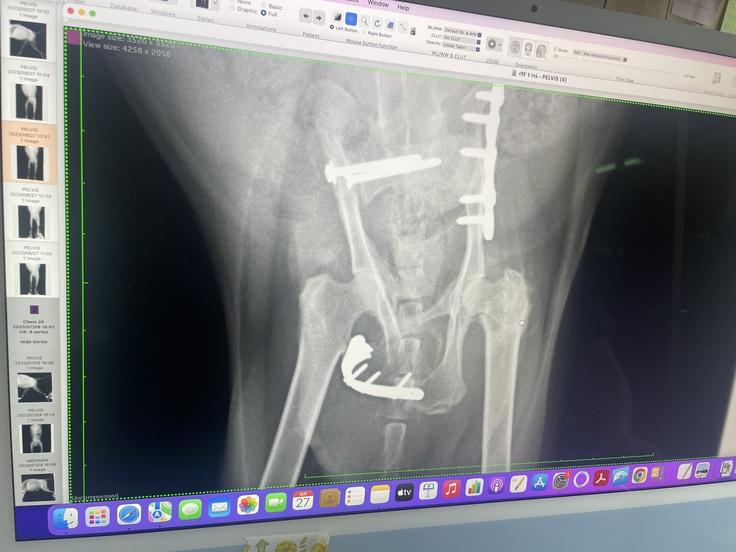

術後1ヶ月経ったのでレントゲンを取りに行きました。

骨を固定していたスクリューが外れてしまい、術後はスクエア型に戻ってましたが、骨がまた内側に入り込んでしまっていました。この状態だと骨で圧迫されて排便が出にくい状況のようで、再度手術が必要かもと言われました。今のとこは様子みて、手術してもらった先生に相談してみるとの事でした。もしかしたらまた費用がかかってしまうかもしれません。可能でしたら更なる支援、snsなどでの拡散の方をお願いしたく思います。再度手術するとなれば合計100万円近くなるかと思われます。費用が足りませんどうかお願いします。